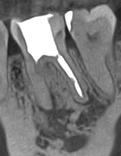

После неудачного лечения каналов в другой клинике у пациентки воспалился зуб внизу слева. Он болел и был под угрозой удаления — нужно было действовать быстро.

Лечение

Мы аккуратно перелечили корневые каналы с помощью микроскопа. Это позволило полностью очистить зуб и дать кости шанс восстановиться.

Результат

Через 6 месяцев кость почти полностью зажила. Зуб сохранен, полностью функционирует и готов к установке коронки.